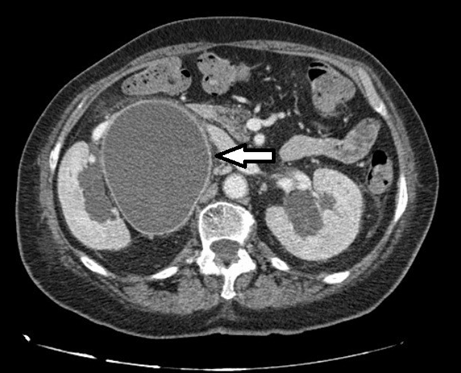

A 70-year-old female presented with right back pain and fever. Six months earlier was submitted to hysterectomy and bilateral salpingo-oophorectomy for an ovarian epithelial cancer (stage IA). On physical examination, she had chills, fever, and tenderness at the right costovertebral angle. Blood tests indicated acute renal failure and marked elevation of C-reactive protein. In renal ultrasound, a mild right hydronephrosis was identified, and the respective ureter proved to be impossible to visualize due to the presence of a large cystic-like structure (19 cm of longitudinal size). As there was a suspicion of obstructive pyelonephritis, a renal scintigraphy was performed indicating the presence of a significant unilateral obstruction. Non-contrast computed tomography (CT) scan showed a markedly distended right ureter (up to 9.5 cm in diameter) with tortuosity (Figure 1) and (Figure 2) (Figure 2), not evident in previous follow-up CT scan. No calculus or other anatomical urologic abnormalities were found. The patient underwent percutaneous nephrostomy, which drained 1500 cc of purulent fluid. Escherichia coli were isolated and adequate antibiotic therapy was instituted. The clinical condition of the patient declined progressively and had passed away after three days.

Figure 1: A cystic-like structure (9.5 cm in diameter) is easily identifiable in the right pararenal location, on the computed tomography scan axial cuts, corresponding to the right ureter.